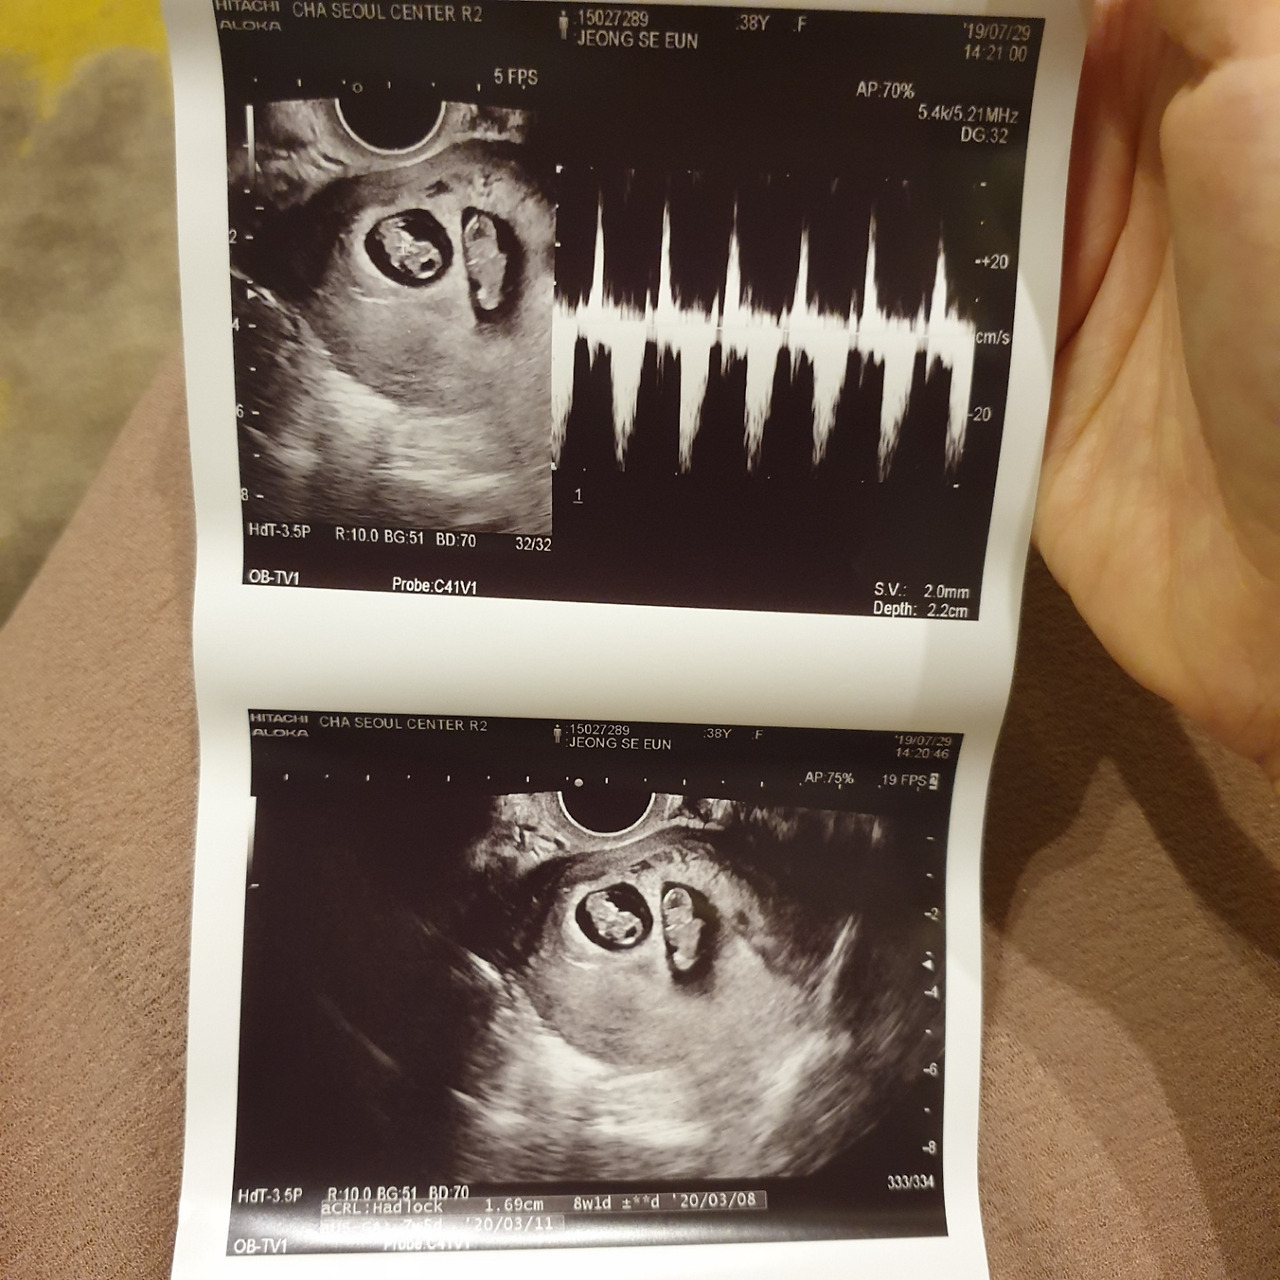

시험관 배아 이식 10일 후, 피검사 수치가 50-100 hCG 이면 안정적인 임신 시작이라 보는데 내 첫 피검사는 150 hCG. 다음 날은 평균의 3배 정도인 400 hCG이라니 뭔가 이상하다. 병원에선 냉정하게 숫자만 알려줄 뿐 질문에 답도 없더니 두 개의 아기집을 보여주며 말한다.

‘쌍둥이네요? 축하드려요.’

매직아이 그림 보듯 뚫어져라 쳐다보는 초음파 사진. 여기가 머리, 이 부분이 다리, 콧날이 높을 것 같아. 1호가 50g 더 크고, 발차기는 2호가 잘하고... 눈으로 레이저를 쏠 수 있다면 초음파 사진들이 이미 구멍나 있을 정도다.